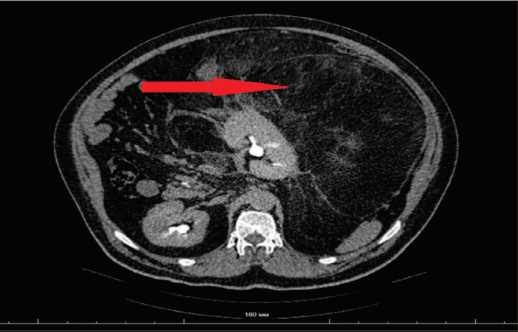

При мультиспиральной компьютерной томографии органов брюшной полости и малого таза с внутривенным контрастированием выявлено объемное новообразование неправильной формы жировой плотности с участками кальцинатов и тканевыми конгломератами, размерами 549×480×339 мм, с плотность в нативной фазе от –102 до +6 ед. HU, которое неравномерно накапливает контрастный препарат: в артериальную фазу – 16 ед. HU, в венозную – 21 ед. HU.

Опухоль компремировала, охватывала и смещала вправо левую почку и левый надпочечник, петли кишечника и поджелудочную железу (рис. 2, 3). В левой половине мошонки определялись множественные варикозно-расширенные вены.

Рис. 3. КТ забрюшинного пространства (ретроперитонеальная опухоль) – аксиальная проекция

Fig. 3. CT scan of the retroperitoneal space (retroperitoneal tumor) – axial projection